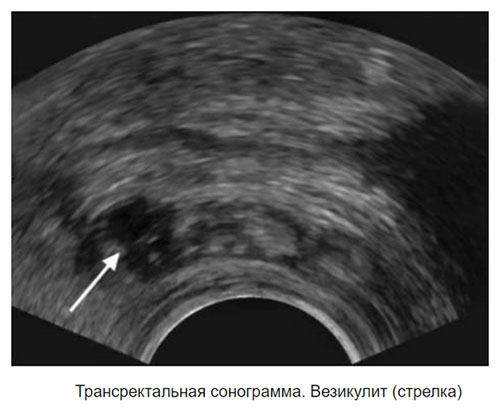

- Трансректальное ультразвуковое исследование (ТРУЗИ) или компьютерная томография (КТ).